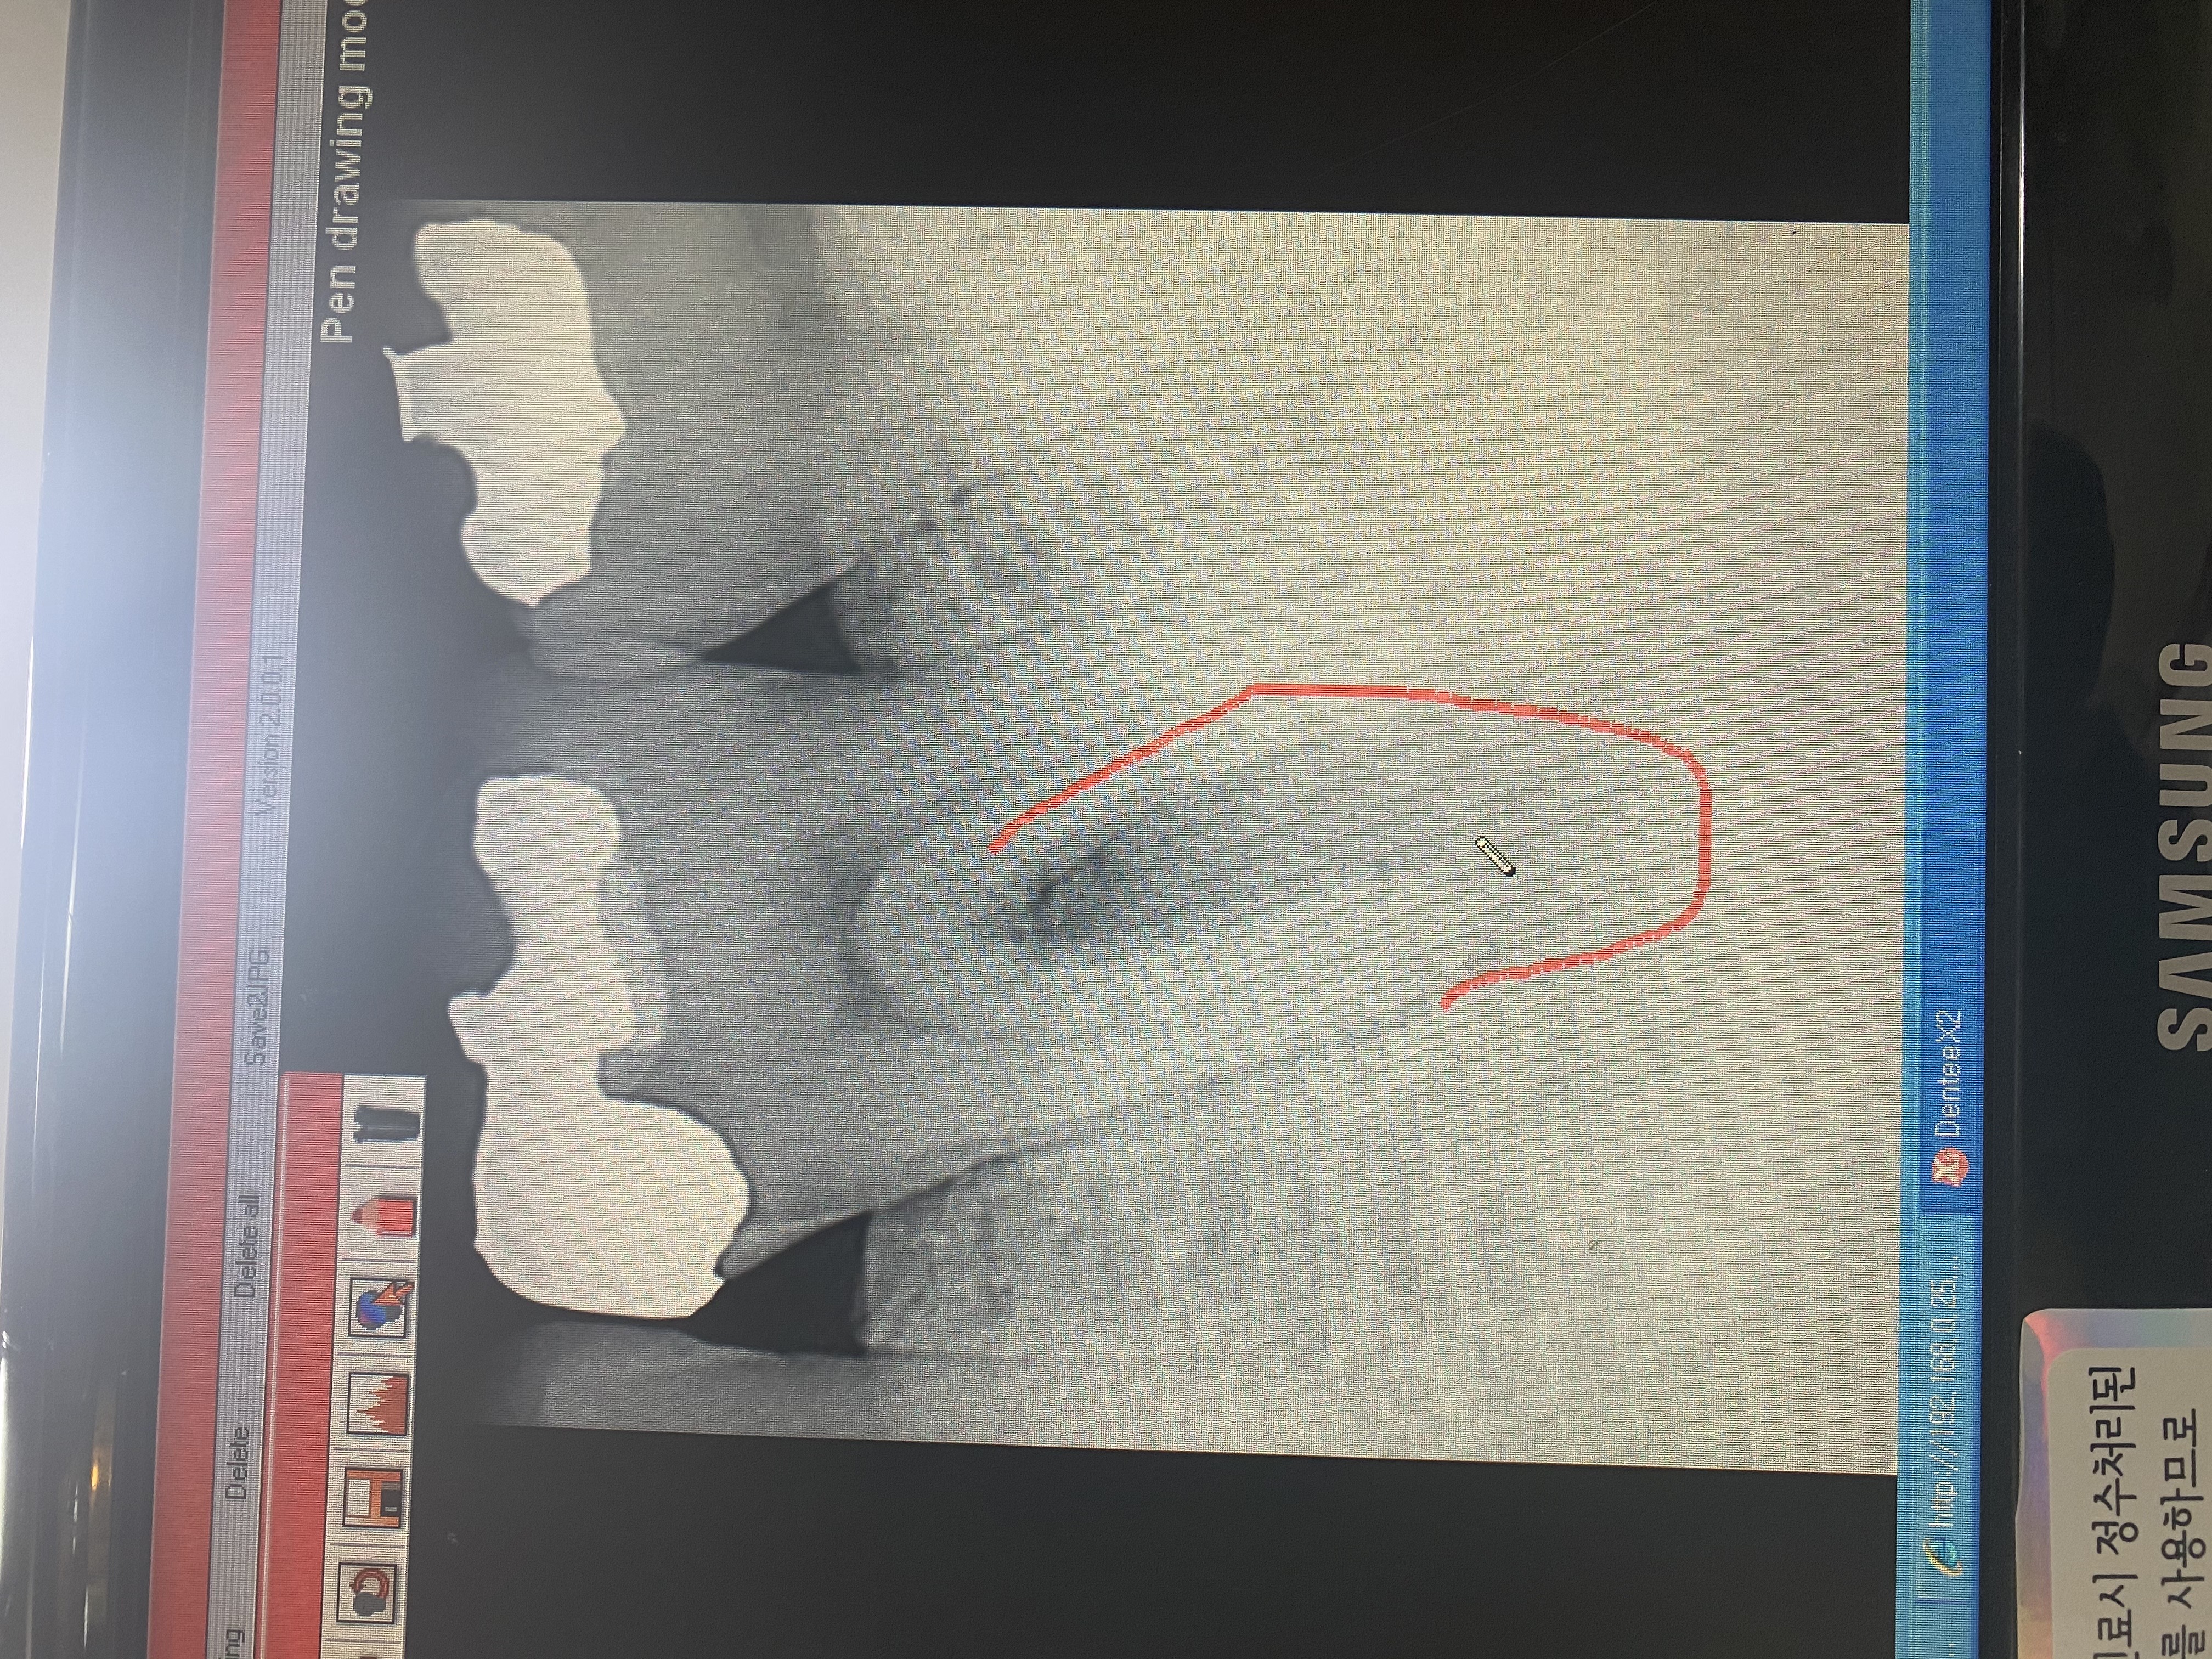

안녕하세요 선생님. 몇해전 선생님 조언으로 많은 도움을 받았었습니다. 이번에 가족이 통증이 있어 치과에 방문했는데 신경치료 또는 임플란트를 추천하더라고요. 제가보기에는 문제의 치아보면 치아부분에는 검게변하지 않아서 충치가 안보이는거 같은데 병원에서는 신경치료나 임플란트를 권하네요. 뿌리끝에도 검은 부분이 없는거 같고요. 뿌리사이에는 검게 염증이 보이는거 같습니다. 사진상으로 정확한 진단은 힘드시겠지만 조언좀 부탁드립니다. 2년전 선생님 말씀대로 신경치로안받고 저도 별다른 통증없이 잘 관리하면서 치아를 사용하고 있어서 항상 감사드립니다.

• 작성자hyuntae 작성자 본인 여부 작성자 | 작성시간 21.05.01 선생님 조언 감사드립니다. 염증이 심한건가요? 보통 검게 나오는게 염증으로 알고 있는데 사진상으로는 뿌리끝은 하얀거 같고 뿌리 사이가 검은거 같은데 그쪽이 염증이 심한건가요?